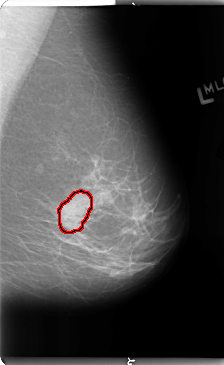

B_3114_1.LEFT_MLO

LEFT_MLO LINES 4744 PIXELS_PER_LINE 2912 BITS_PER_PIXEL 12 RESOLUTION 50 OVERLAY

FILE: B_3114_1.LEFT_MLO.OVERLAY

TOTAL_ABNORMALITIES 1

ABNORMALITY 1

LESION_TYPE MASS SHAPE LOBULATED MARGINS CIRCUMSCRIBED-ILL_DEFINED

ASSESSMENT 4

SUBTLETY 3

PATHOLOGY BENIGN

TOTAL_OUTLINES 1

BOUNDARY